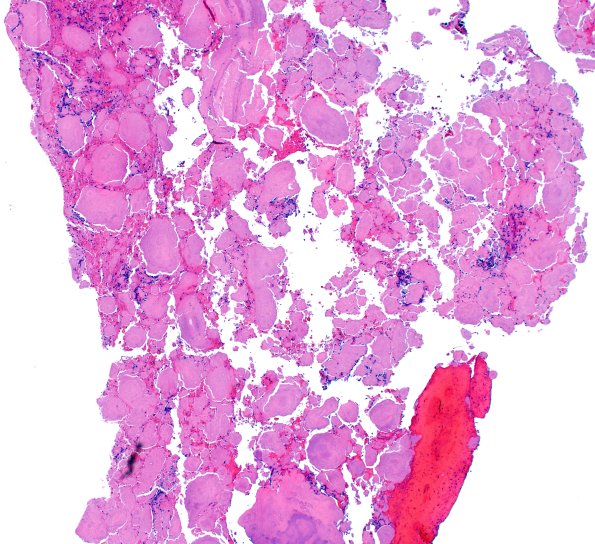

Washington University Experience | MISCELLANEOUS | Amyloidoma | 7B1 Amyloidoma (Case 7) H&E 4X

Hematoxylin and stained sections show abundant globules of amorphous eosinophilic acellular material. The material shows focal calcifications. (H&E)